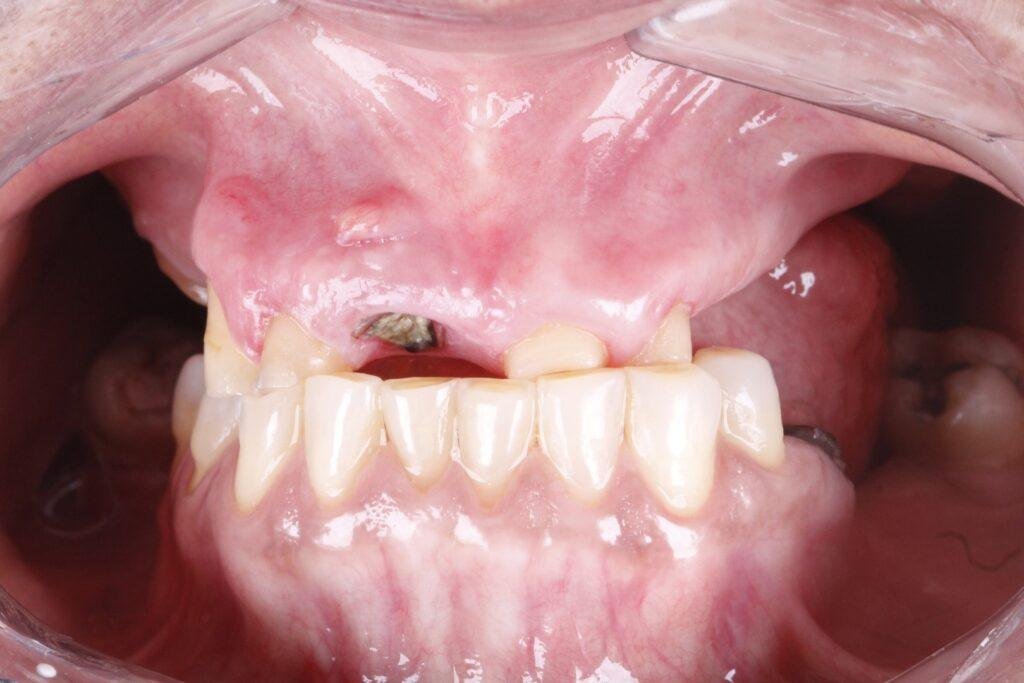

O All-on-Four é um protocolo de implantes dentários que utiliza apenas 4 implantes para fixar uma prótese total, substituindo todos os dentes da arcada.

Diferente de técnicas convencionais, não exige enxertos ósseos na maioria dos casos, tornando o tratamento mais rápido e confortável.

É uma técnica moderna que utiliza apenas 4 implantes estrategicamente posicionados para suportar uma prótese fixa, devolvendo função mastigatória, estética e conforto sem necessidade de enxertos.

Na maioria dos casos, não. O All-on-Four dispensa enxertos, oferecendo um procedimento mais rápido, seguro e menos invasivo.

Em muitos casos, é possível instalar dentes fixos no mesmo dia da cirurgia. Isso significa que o paciente recupera a estética do sorriso e a função mastigatória muito mais rápido do que em técnicas convencionais.

Segundo o Dr. Arnaldo, pioneiro em Belém na técnica do All-on-Four, o tratamento com implantes, especialmente a prótese protocolo, vai muito além da cirurgia.

Planejamento minucioso, cada caso é estudado em detalhe, respeitando as necessidades e particularidades de cada paciente.

Execução precisa, técnicas avançadas e seguras garantem conforto durante o procedimento e resultados previsíveis.

Acompanhamento contínuo, revisões e manutenções periódicas são fundamentais para preservar a saúde bucal e prolongar a vida útil da prótese.